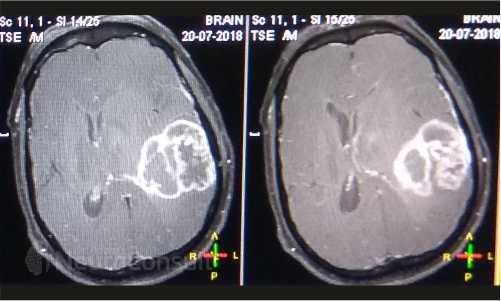

My Cases Studies & Work